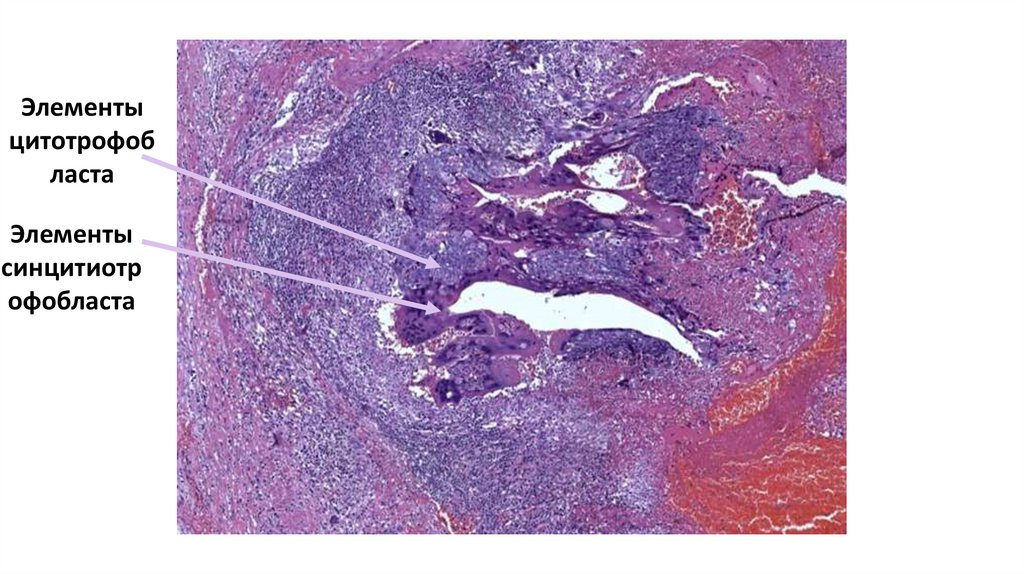

8. Лимфатический узел при лимфоме Ходжкина

Клетка

Ходжкина

РидБерезовскогоШтернберга